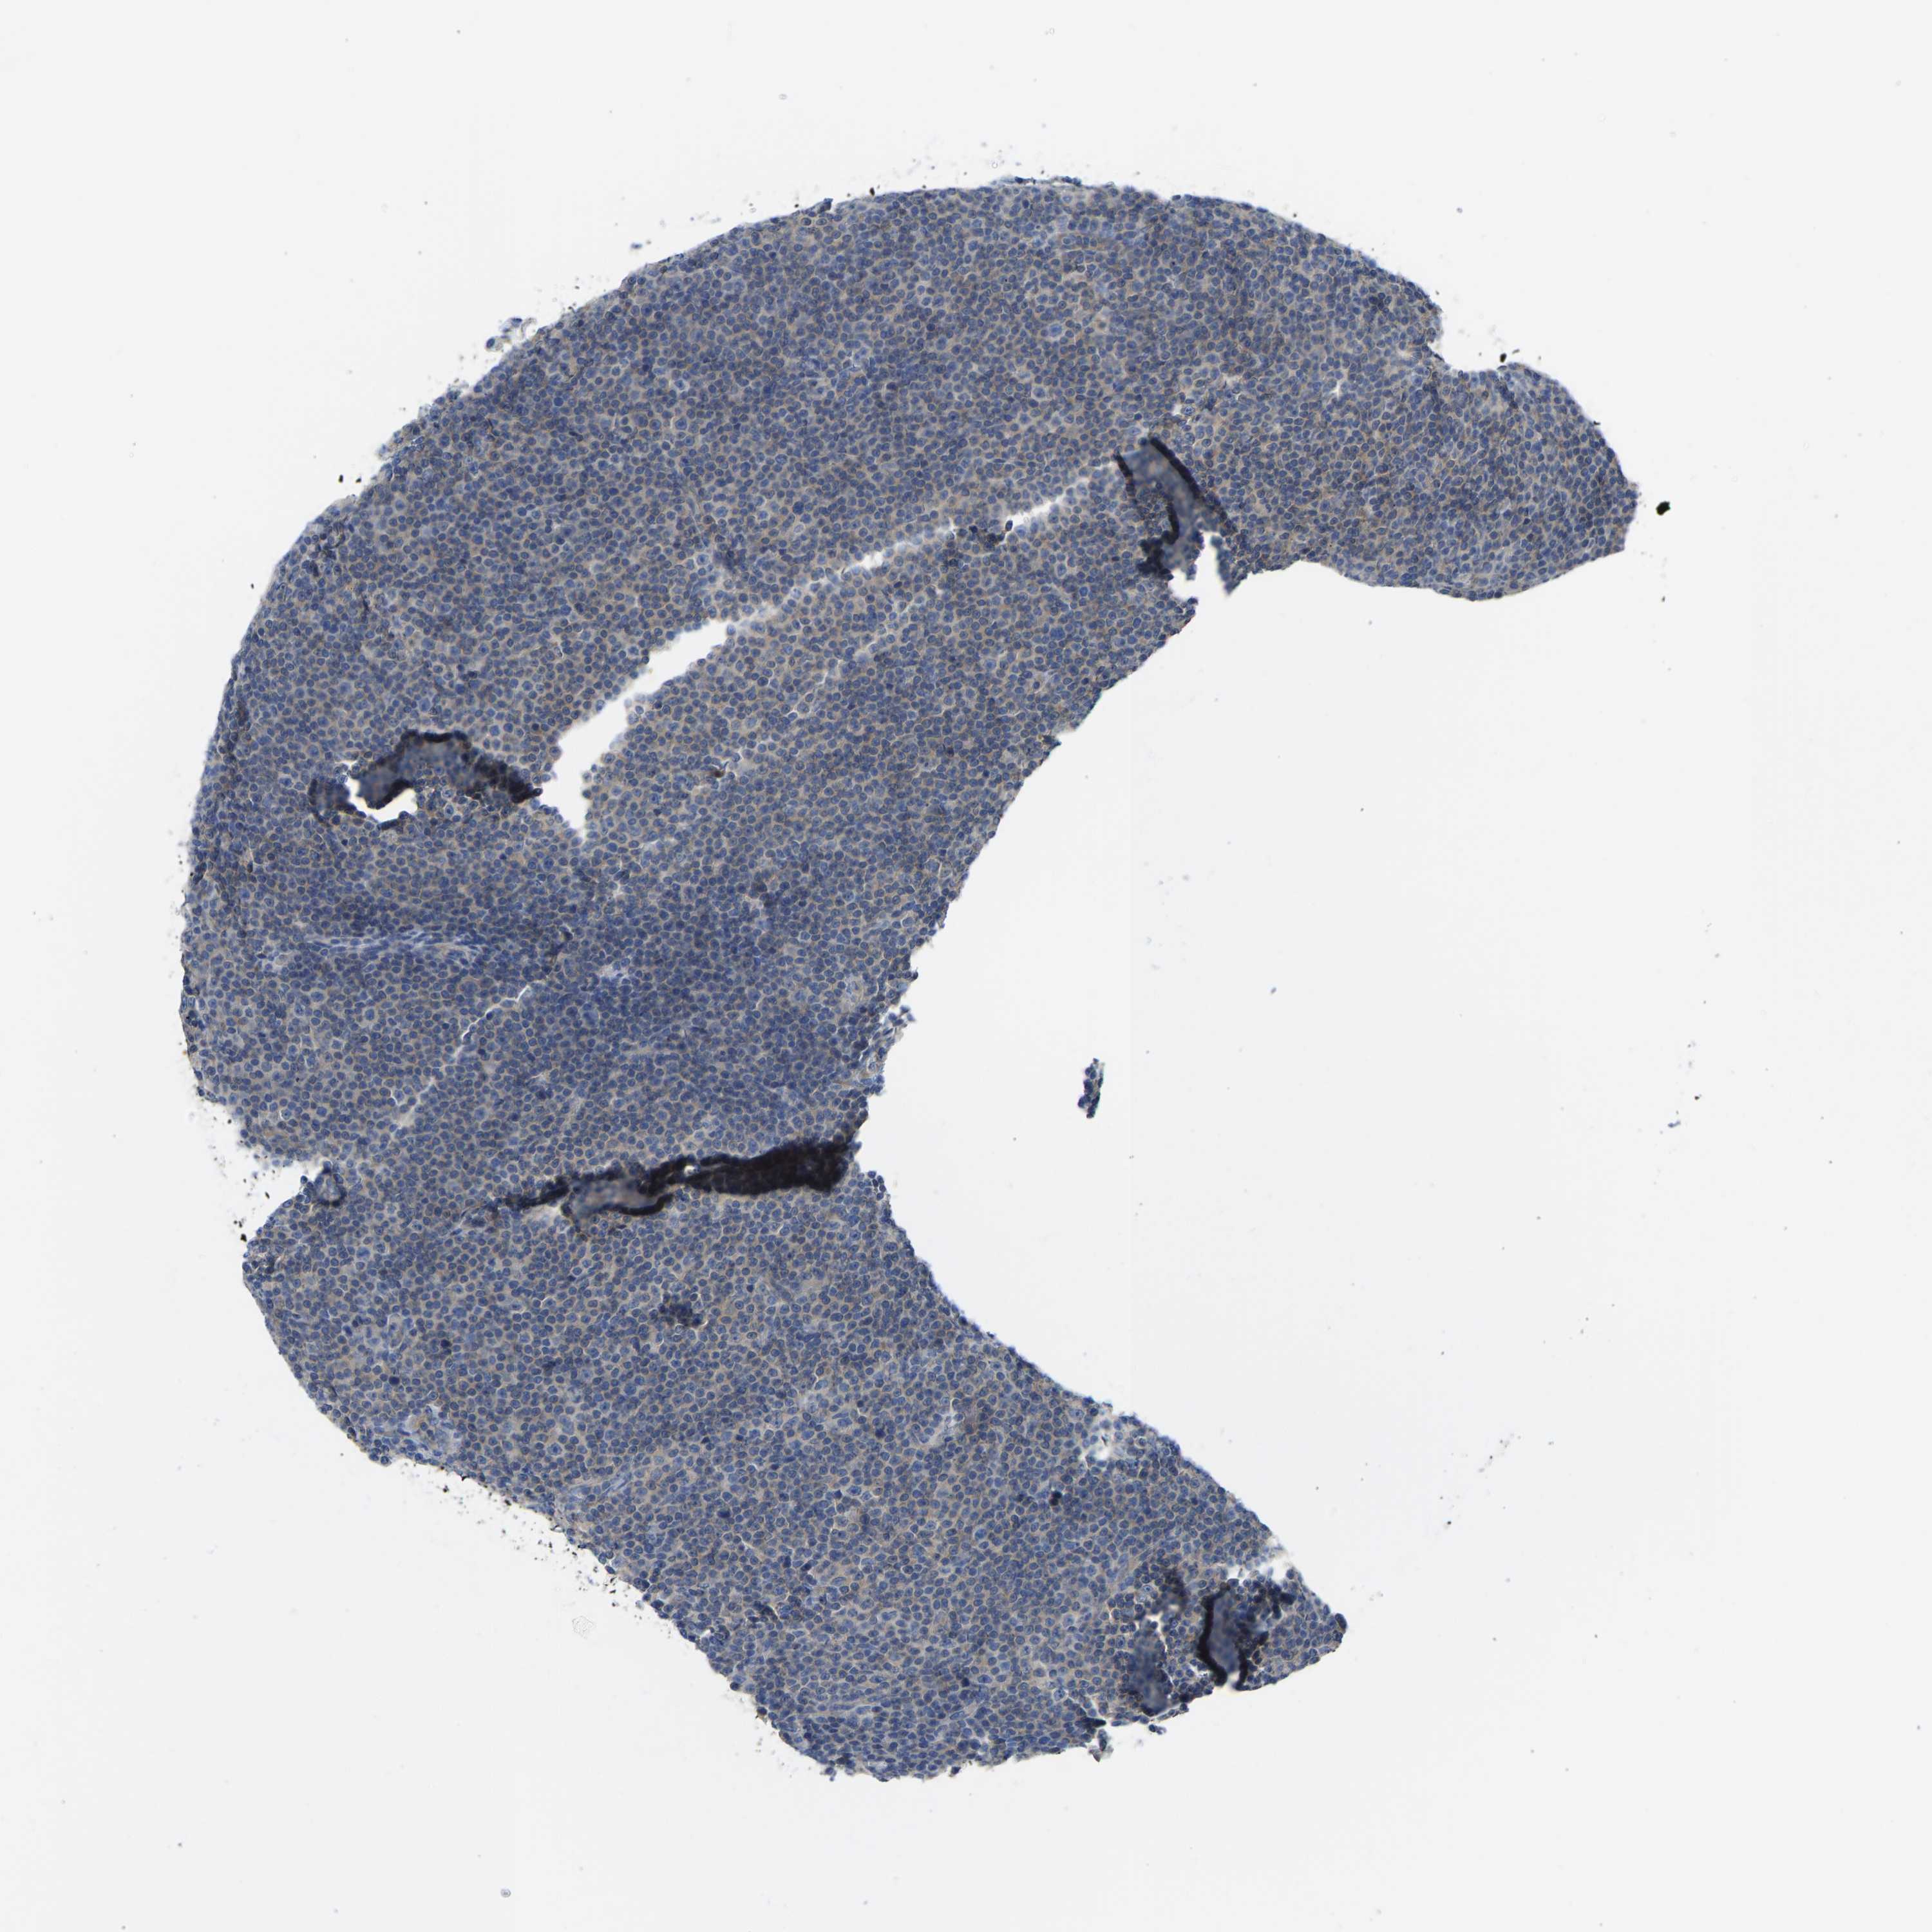

CANCER LYMPHOMA Show tissue menu

LYMPHOMA - Protein expressioni

A mouse-over function shows sample information and annotation data. Click on an image to view it in a full screen mode. Samples can be filtered based on level of antibody staining by selecting one or several of the following categories: high, medium, low and not detected. The assay and annotation is described here.

Antibody stainingi

Antibody staining in the annotated cell types in the current human tissue is reported as not detected, low, medium, or high, based on conventional immunohistochemistry profiling in selected tissues. This score is based on the combination of the staining intensity and fraction of stained cells.

Each image is clickable and will lead to virtual microscopy that enables deeper exploration of all samples and also displays staining intensity scores, fraction scores and subcellular localization as well as patient and tissue information for each sample.

Antibody HPA012778

Antibody CAB018581

Staining

High

Medium

Low

Not detected

Intensity

Strong

Moderate

Weak

Negative

Quantity

>75%

75%-25%

<25%

None

Location

Nuclear

Cytoplasmic/membranous

Cytoplasmic/membranous,nuclear

Hodgkin's disease, NOS

Malignant lymphoma, non-Hodgkin's type, High grade

Malignant lymphoma, non-Hodgkin's type, Low grade